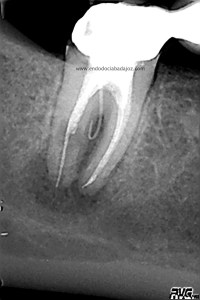

Acude a nuestra clínica una paciente que llamamos a revisión después de realizarle un retratamiento endodóntico de la pieza 4.7 hace unos meses. Si recordamos el día que llegó, no se nos presentaba muy bien el caso, y como otros muchos casos, intentamos retratarlo, pues pensamos que podríamos manejarlo.

Este caso lo resolveríamos en varias sesiones, después del manejo de los conductos mesiales, con una preparación biomecánica terminando en una conicidad del 6% y un diámetro apical de 30 en conductos mesiales.

Con ayuda del microscopio, pudimos confirmar que se trataba de una reabsorción interna en el tercio medio y una reabsorción radicular del conducto distal.

Bueno, pues el conducto distal se obturó en su tercio apical y medio con M.TA.